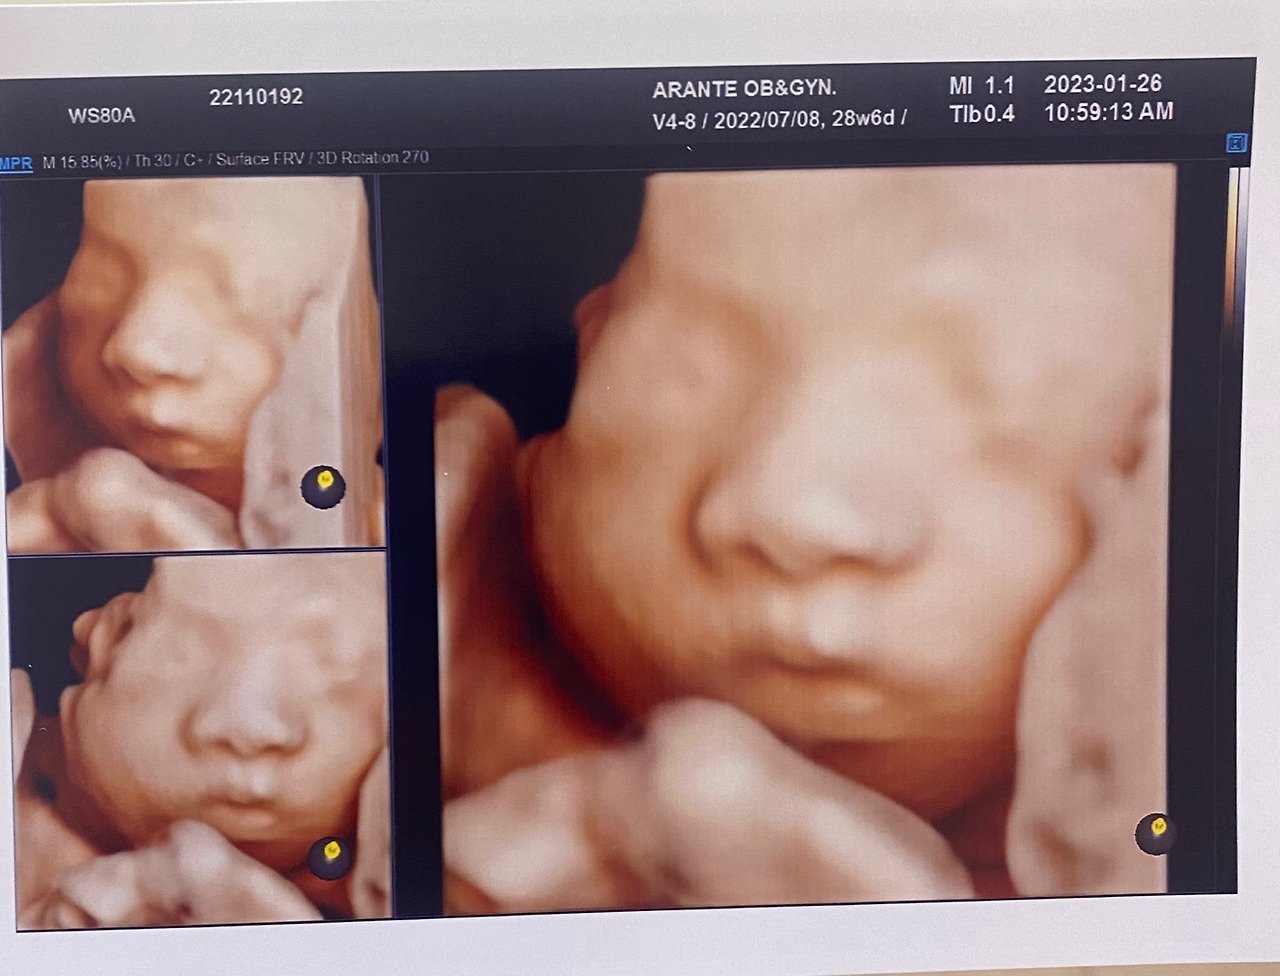

KakaoTalk_20230413_190017657_04.jpg 입체 초음파 사진을 통해 아기의 얼굴을 볼 수 있다.